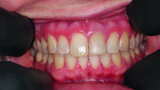

Fig. 17: Complete preservation of the vestibular contour.

Fig. 18: Final image immediately after inserting the crown with an ideal red–white aesthetic.